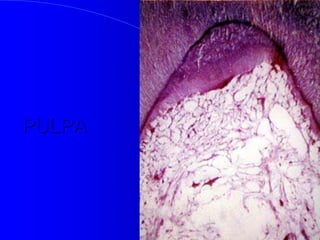

PULPA

Componentes Estructurales

De La Pulpa

 Tejido conectivo de variedad Laxa,

vascularizado

 Rodeada de odontoblastos en su periferia y

dentina mineralizada